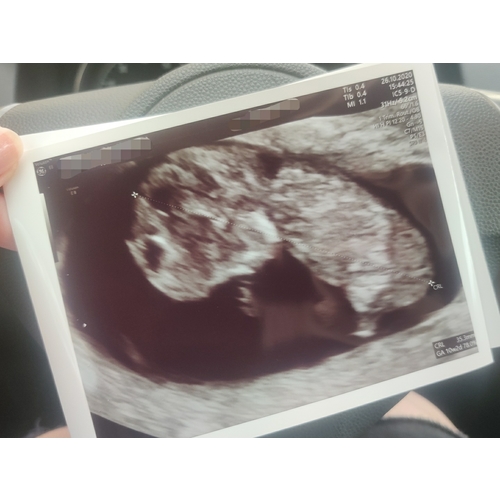

Dit was met precies 11 weken, je ziet echt al een heel mensje 💖

Oh bij jou kun je al zien wat het wordt 😊Ik zeg niks hoor 🙊